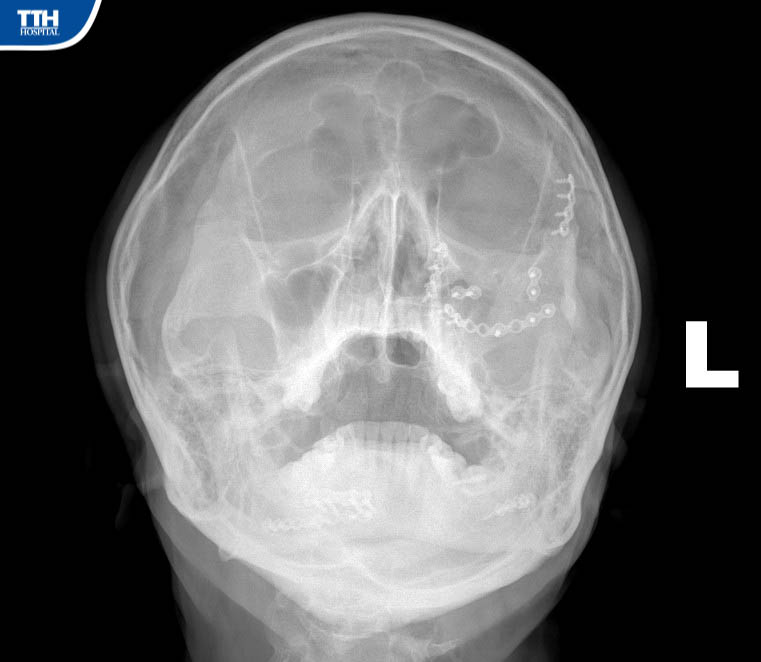

Vừa qua, Bệnh viện Đa khoa TTH Hà Tĩnh tiếp nhận bệnh nhân H.Đ.H (47 tuổi, Hương Khê, Hà Tĩnh), bệnh nhân cho biết lý do nhập viện khoa Răng Hàm Mặt là vì: ‘‘Cách đây 15 tháng đã đến Bệnh viện Hữu Nghị Việt Đức mổ kết hợp xương vùng hàm mặt, trước khi ra viện các Bác sĩ phẫu thuật nói: khi nào tháo nẹp vít thì ra Hà Nội tháo chứ tuyến dưới không tháo được". Đã đến kỳ hạn tháo nẹp vít kết hợp xương, qua tìm hiểu và được người nhà giới thiệu nên tôi quyết định đến Bệnh viện Đa khoa TTH Hà Tĩnh để tháo’’.

Theo BSCKI Trần Đức Hải – Khoa Răng Hàm Mặt Bệnh viện Đa khoa TTH Hà Tĩnh cho biết: ‘‘Ca phẫu thuật tháo phương tiện kết hợp xương phức tạp, gãy cả xương hàm trên trái và gãy xương hàm dưới 2 bên đòi hỏi kíp phẫu thuật có trình độ chuyên môn sâu về lĩnh vực hàm mặt, bởi gần như các đường rạch đều được dấu kín bằng đường trong miệng để tránh tạo sẹo ngoài da ’’.

‘‘Ca phẫu thuật diễn ra thuận lợi trong khoảng gần 90 phút. Sau phẫu thuật tháo phương tiện kết hợp xương hàm mặt, người bệnh hồi phục nhanh, từ ngày thứ 2 sau mổ. Sau 3 ngày, người bệnh có thể đi lại, sinh hoạt và xuất viện’’. Bs Hải cho biết thêm.